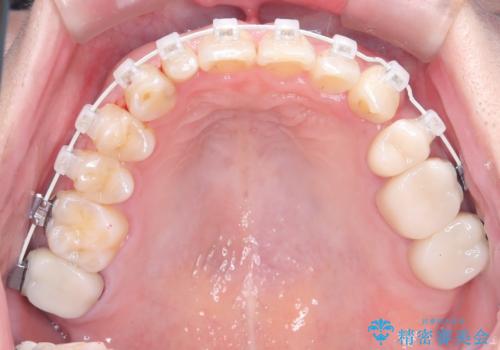

40代は歯周組織の健康維持も重要なため、無理な拡大を避け、左上4番(第一小臼歯)を抜歯して確実にスペースを確保する計画を立てました。装置には、歯を三次元的にしっかりとコントロールでき、確実な移動が見込めるワイヤー矯正を選択。八重歯を正しい位置へ誘導し、健康的で美しい口元を目指しました。

まず、計画通り左上4番を抜歯し、そのスペースを利用して八重歯を徐々に正しい位置へと移動させました。ワイヤー矯正特有の「歯を細かく、確実に動かす力」を最大限に活用し、歯根の向きまで丁寧に調整。